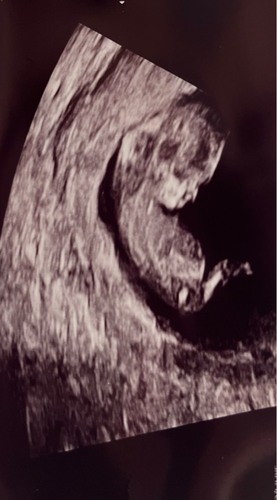

11.1 week. Jongen of meisje?

Nou iemand een idee🫣

Meisje